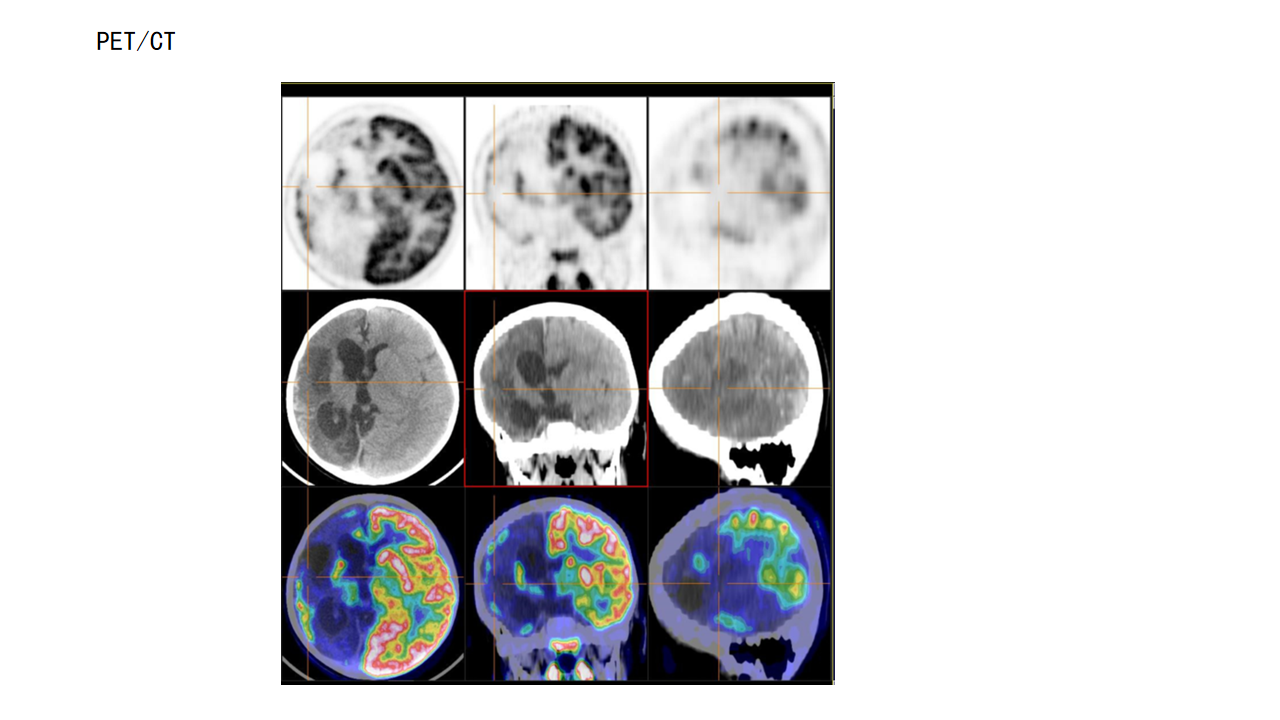

右侧功能性大脑半球切除术

杨文桢

兰州大学第二医院